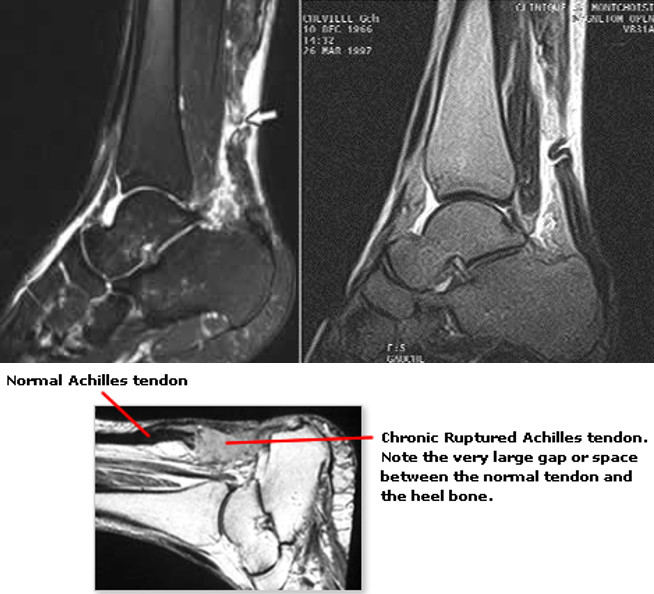

辅检:MRI、X线片、超声等。

B超或核磁共振(MRI)检查,可以明确损伤位置。